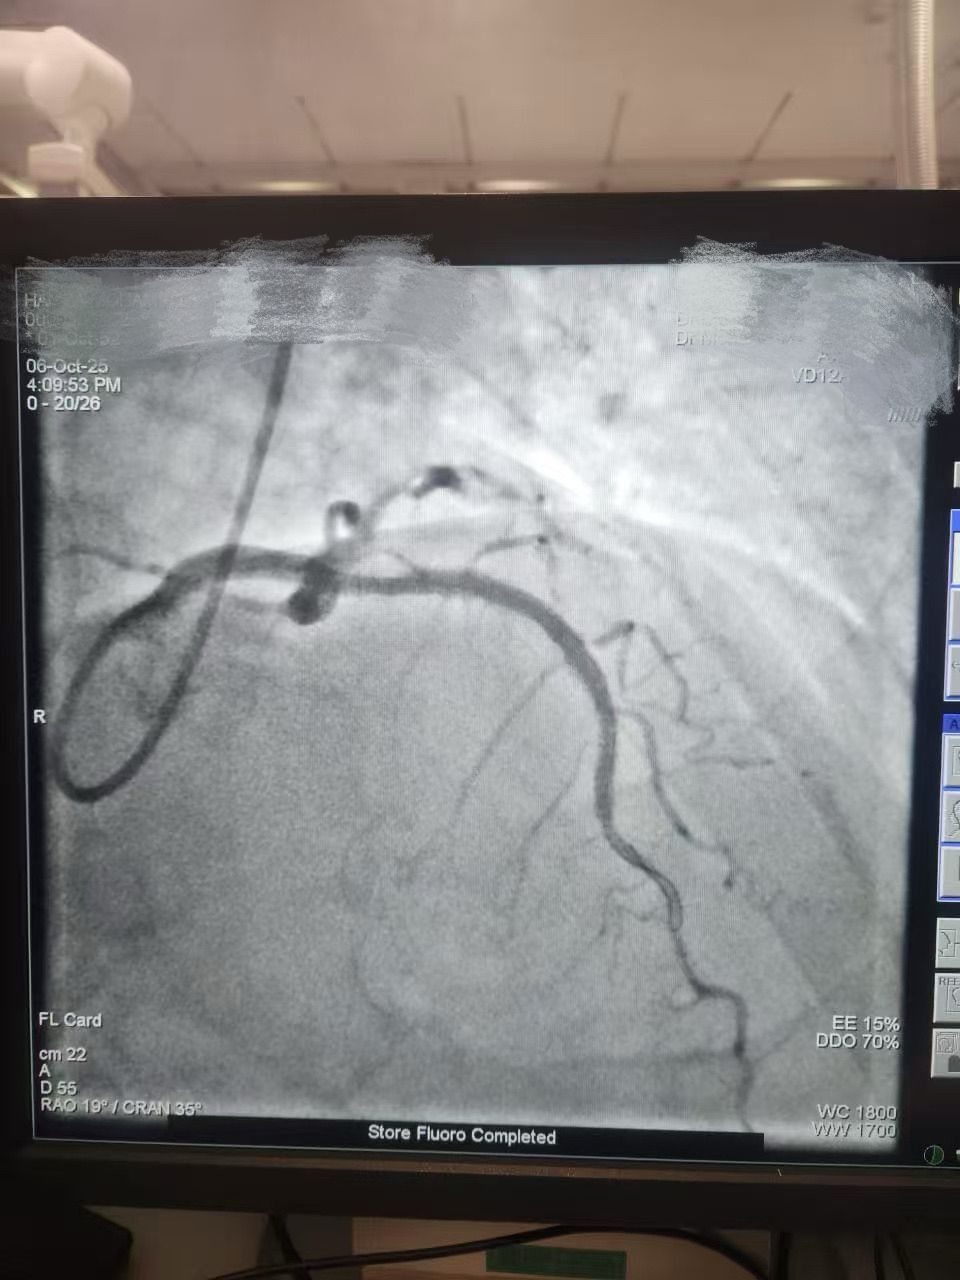

We are proud to share a successful clinical case from HMS Mirdif Hospital, UAE, where Dr. Mohamed Houcem Amiour and his exceptional Cath Lab team — Ambily Mathew, Aswathy S Babu, Geethanjali Rema Suresh, and Mathew Philip — successfully performed a PTCA to the LAD using Lepu Medical's Vesscrack Coronary IVL Balloon System.

To achieve optimal lesion preparation and stent expansion, the team skillfully combined Rotablator with Lepu's IVL, ensuring precise and effective calcium modification.

It demonstrates how Lepu's IVL technology delivers powerful calcium modification performance, supporting physicians in achieving safe and efficient outcomes in complex coronary interventions. A huge thank-you to Dr. Amiour and his incredible Cath Lab team for their trust in Lepu Medical.